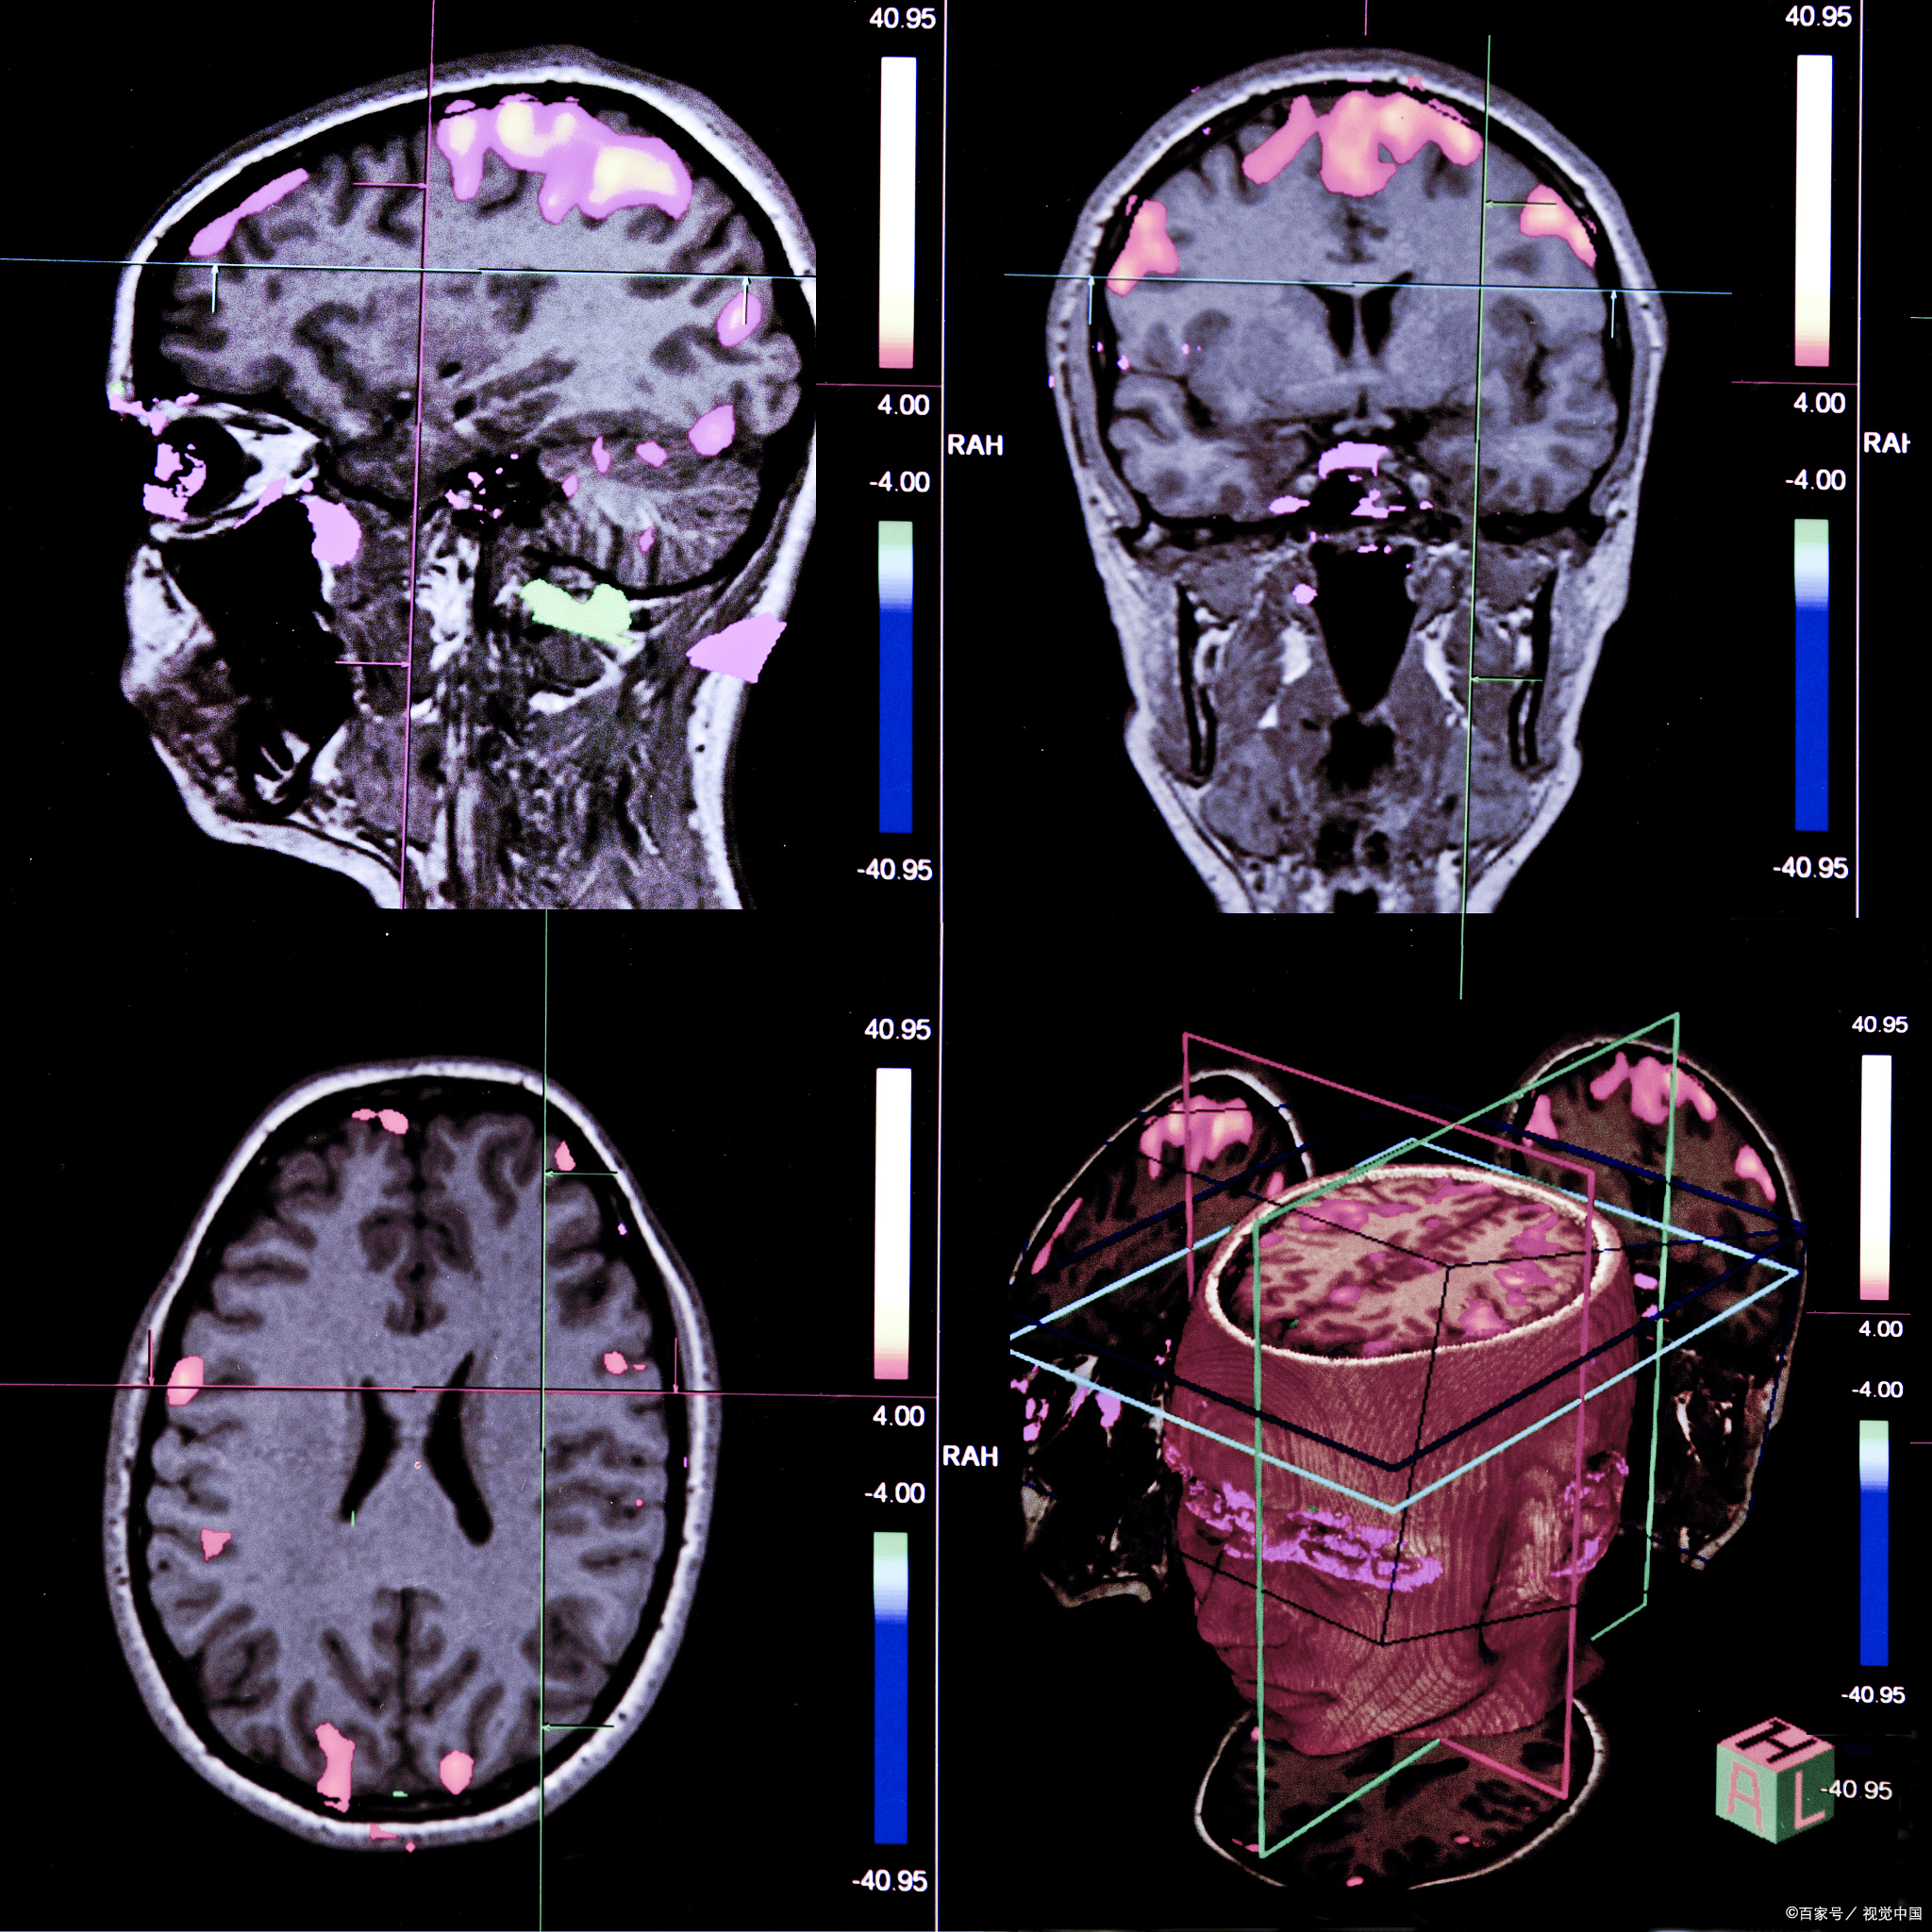

多模态光学成像技术结合多种成像模态,全面,精准检测生物组织结构和

可以通过成像技术观察和记录脑部结构和功能上的变化

创新组织透明技术在无标记脑成像的应用

慧创近红外助力青少年抑郁症常规检查